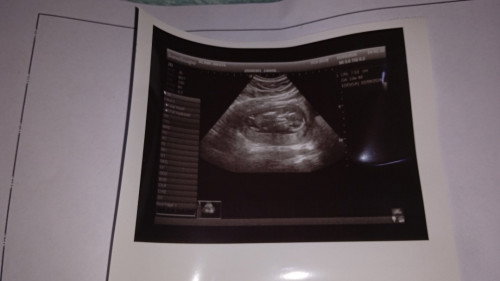

hallo bunda bunda semua, aku kan baru usg di usia kehamilan 13-14 minggu ini, sudah terlihat janinnya, dan djj di 140 alhamdulillah katanya normal, cuma tadi kena tegur sama dokternya bunda bunda, karena aku memaksakan puasa, jadi pas tadi usg dede bayi nya keliatan lemes;( udah gitu cairan ketubannnya katanya kurang;( dan harus banyak minum. aku mau tanya, bunda bunda disini ada yang sama kek aku ga? apa bunda bunda masi melakukan puasa atau tidak? terimakasih bunda bunda#mohonbantujawabbunda